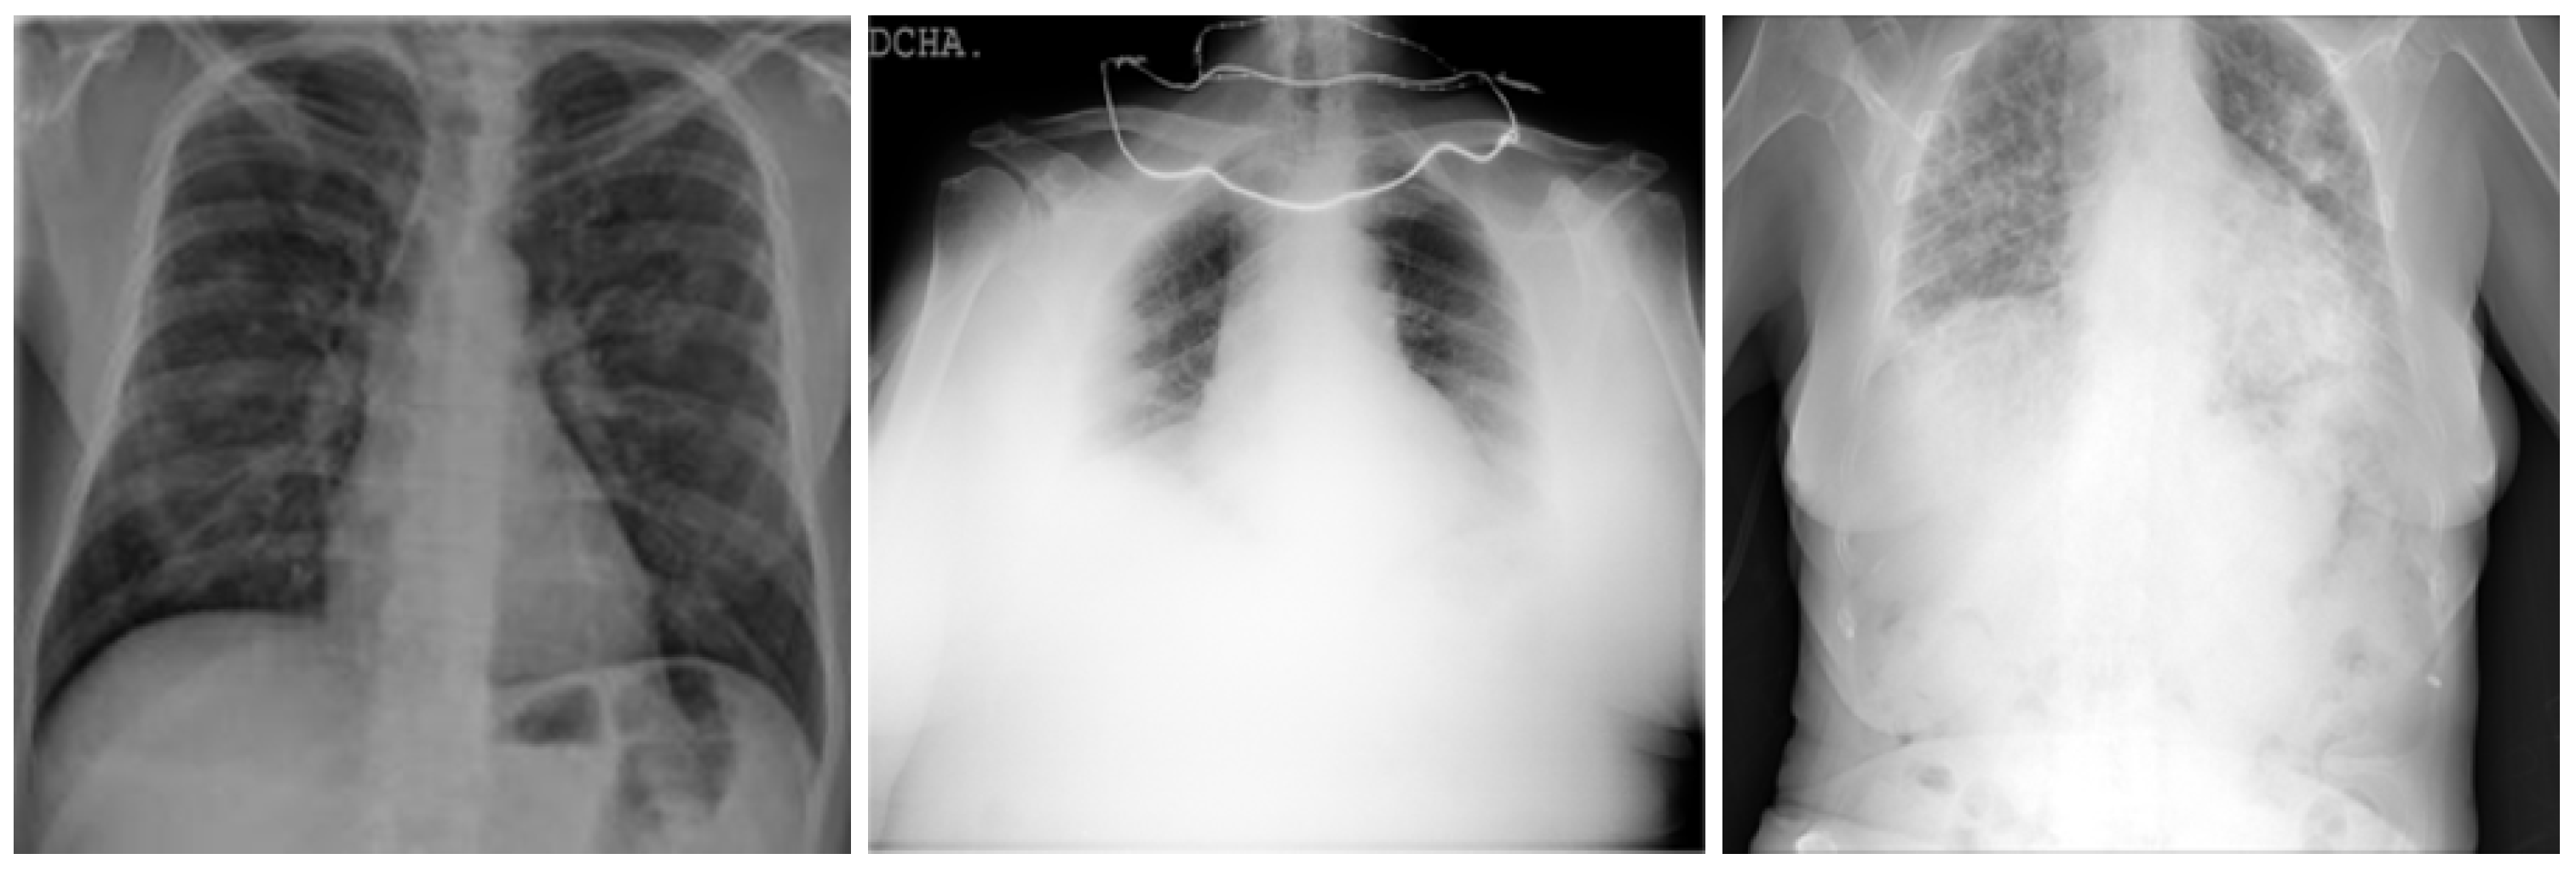

In this work, a COVID-19 radiography dataset collected in previous works related to a COVID-19 detection model [24,25] was used. The dataset contains X-ray lung images with four different classifications, which are COVID, Lung_OPACITY, Normal, and Viral Pneumonia. In this work, we utilized two classifications, which are COVID and Normal, focusing only on the COVID-19 detection machine learning process.

Figure 3.

COVID-19 positive X-ray image dataset samples.